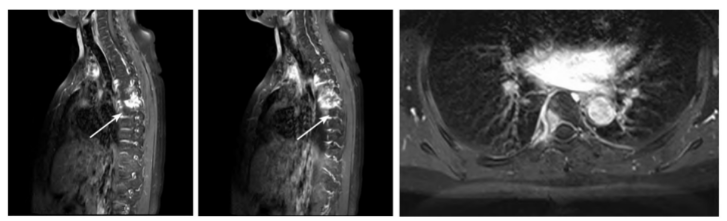

病人于门诊行胸腰椎MRI示T6及L1椎体异常信号,建议增强扫描分析(见图2)。

图2 胸腰椎MRI。T6椎体右后缘、L1椎体前下缘见斑片状长T1等及稍短T2信号,压脂相呈高信号

完善胸腰椎MRI增强扫描提示T6椎体及邻近附件、肋骨及L1椎体伴周围软组织异常强化影,考虑炎性病变(见图4、5)。

图4 胸腰椎MRI增强扫描。箭头所指为T6椎体及邻近附件,可见斑片状明显强化影,累及相应肋骨头